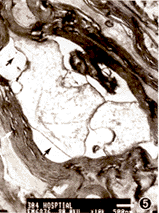

损伤后7天,G1组轴突变稀疏,呈空泡状或网状。轴突与髓鞘间有空泡形成,髓鞘有部分向内、向外突起,髓鞘板层分裂(图5)。G2组轴突未见明显异常,髓鞘有轻度板层分裂(图6)。

图5 损伤7天,G1组轴突稀疏呈空泡状或网状与髓鞘间有空泡形成(黑箭头),髓鞘内突或外突并可见板层分裂(白箭头)×10 000